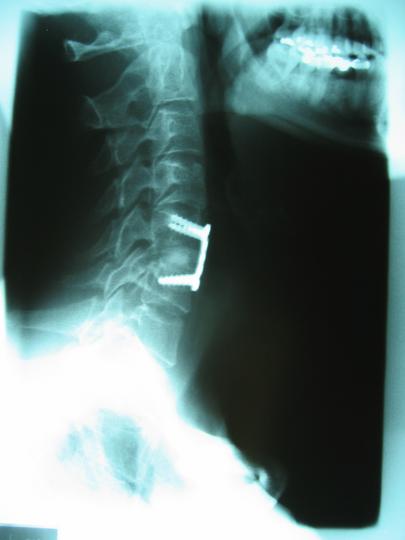

Cervical Fusion, C5/C6; side view

You'd think for ten grand he could bolt it on straight: